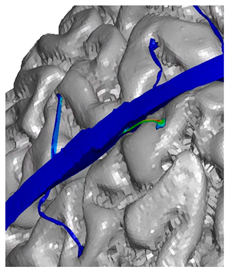

| Frontal veins |  |  |  |

| Parietal veins |  |  | |

| Occipital veins |  |  |